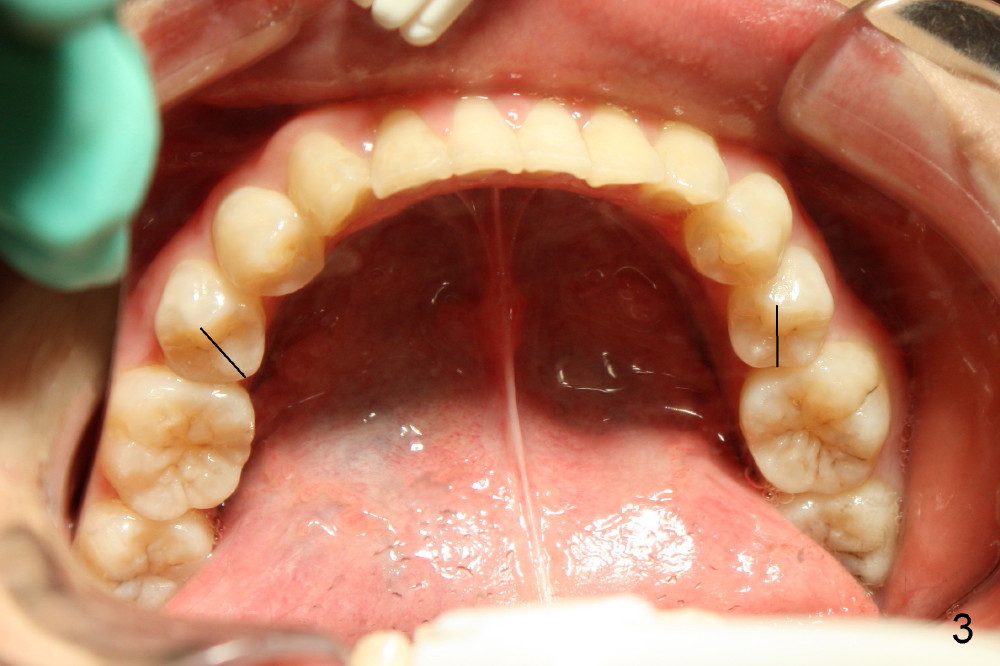

Ms. Xu, 16 years old, has bilateral posterior and UL 2 cross bite (Fig.1,2). L5s rotate (Fig.1-3: black lines).